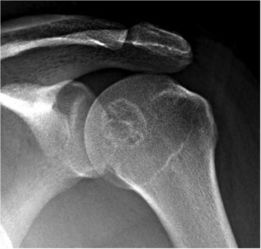

软骨母细胞瘤

软骨母细胞瘤可发生于肩部,肿瘤多生长在骨骺内,症状有些类似于邻近节段的关节紊乱,表现为局部的胸背部疼痛,可有放射痛。